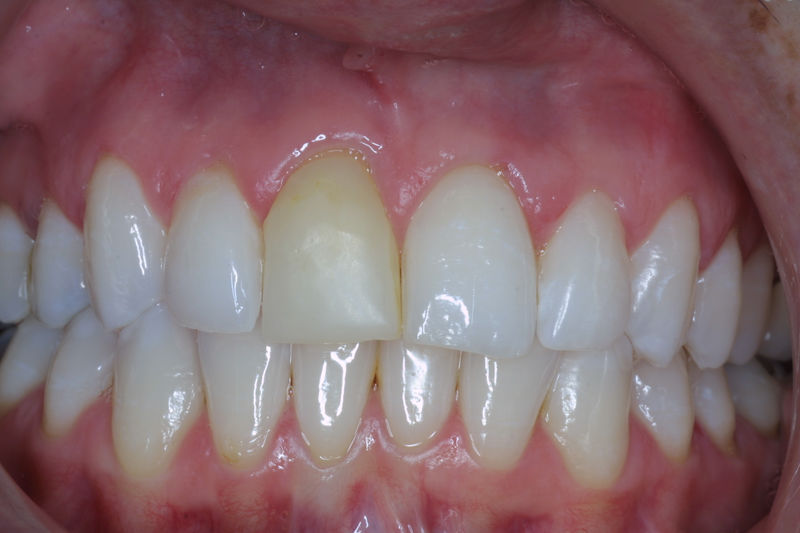

Amplia gama de tratamientos para mejorar la apariencia de la sonrisa, corrigiendo el color, la forma, el tamaño, la alineación y la posición de los dientes. Los procedimientos más comunes y solicitados incluyen el blanqueamiento dental, las carillas y coronas, así como las resinas.

Son restauraciones que cubren toda la cara frontal del diente, generalmente empleadas en el sector anterior y cuya finalidad es primariamente estética.

Restauraciones fabricadas en el laboratorio con materiales estéticos, los cuales cubren de manera total dientes anteriores y posteriores. Se utilizan primariamente para restaurar dientes con caries, fracturas y/o defectos amplios, así como soportes de puentes. Para poder enviar el caso al laboratorio se toman impresiones utilizando materiales de impresión o técnicas modernas digitales.

Ortodoncia y coronas.